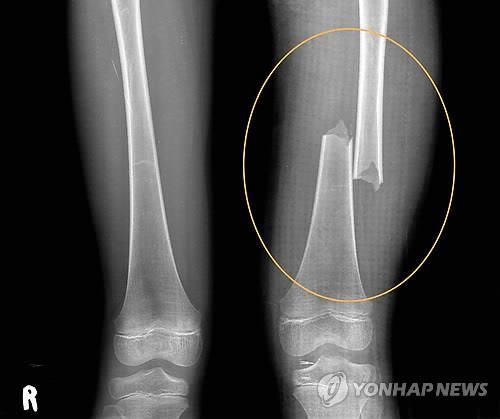

계모 학대로 허벅지 뼈가 두 동강 난 서현이 사진 계모 학대로 허벅지 뼈가 두 동강 난 서현이 사진

[연합뉴스 자료사진]

서현이는 계모인 엄마에게 5년 동안 고문보다 더한 학대를 받았다. 초등학교 1학년 때 몸에서 가장 단단하다는 허벅지 뼈가 두 동강이 났고, 같은 해 10월에는 양손과 발등, 정강이에 피부 이식 수술을 해야 하는 2도 화상을 입었다. 모두 계모 박씨의 짓이었다.